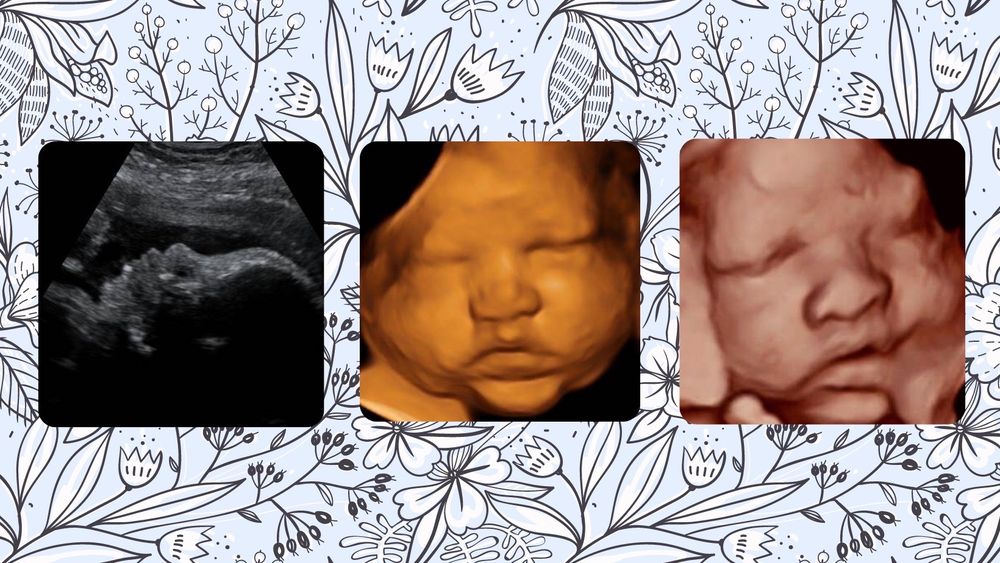

From www.facebook.com

Teaching Tuesday.... Radiology and MRI of Bethlehem, Inc Radiology And Mri Of Bethlehem Fax Number The provider is registered as an organization entity type and is a single. Is 5325 northgate dr suite 100 bethlehem, pa. The current location address for radiology & mri of bethlehem, inc. Table includes a list of all field names, values and definitions. The contact telephone number is. Radiology & mri of bethlehem can be contacted. Provider in 5325 northgate. Radiology And Mri Of Bethlehem Fax Number.

From www.yelp.com

FIRST LOOK IMAGING Ultrasound Imaging Centers Bethlehem, PA Phone Number Yelp Radiology And Mri Of Bethlehem Fax Number Data available for download in csv. Radiology & mri of bethlehem, inc. Provider in 5325 northgate dr suite 100 bethlehem, pa 18017. Is 5325 northgate dr suite 100 bethlehem, pa. Radiology & mri of bethlehem is located at 5325 northgate dr in bethlehem, pennsylvania 18017. Radiology & mri of bethlehem, inc. The contact telephone number is. Complete dataset for npi. Radiology And Mri Of Bethlehem Fax Number.